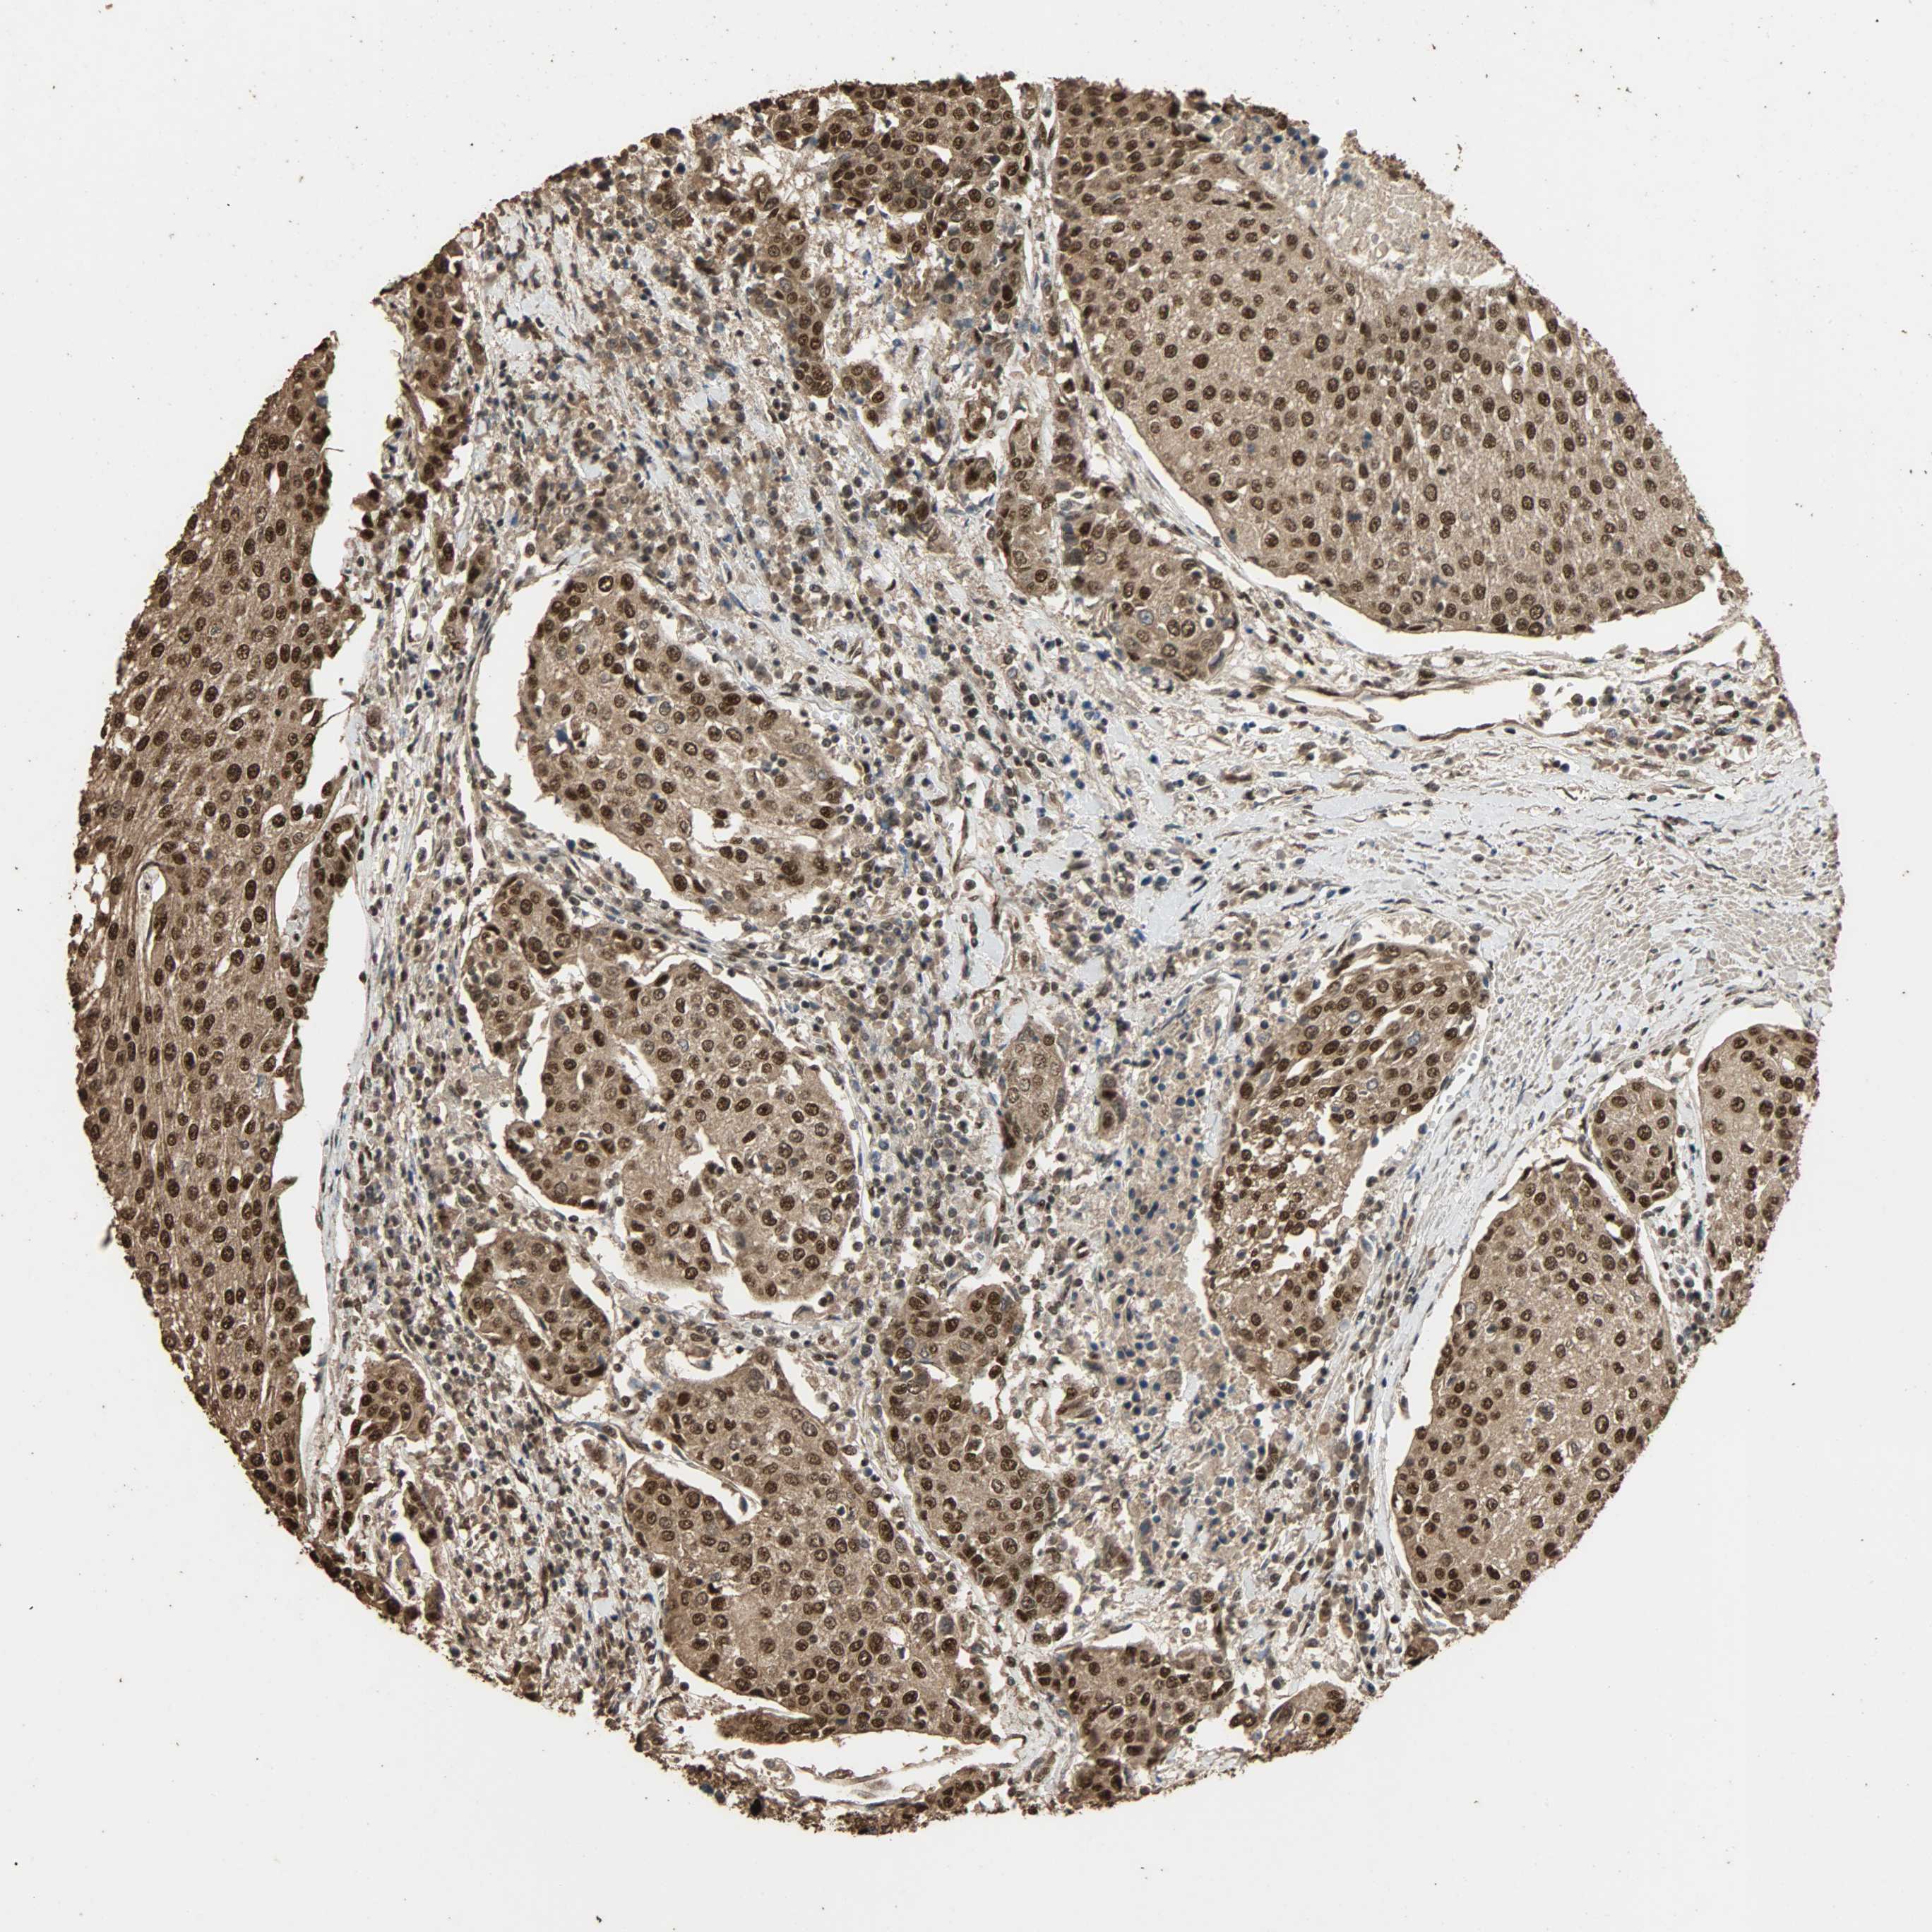

UROTHELIAL CANCER - Protein expressioni

A mouse-over function shows sample information and annotation data. Click on an image to view it in a full screen mode. Samples can be filtered based on level of antibody staining by selecting one or several of the following categories: high, medium, low and not detected. The assay and annotation is described here.

Note that samples used for immunohistochemistry by the Human Protein Atlas do not correspond to samples in the TCGA dataset.

Antibody stainingi

Antibody staining in the annotated cell types in the current human tissue is reported as not detected, low, medium, or high, based on conventional immunohistochemistry profiling in selected tissues. This score is based on the combination of the staining intensity and fraction of stained cells.

Each image is clickable and will lead to virtual microscopy that enables deeper exploration of all samples and also displays staining intensity scores, fraction scores and subcellular localization as well as patient and tissue information for each sample.

Antibody HPA005559

Staining

High

Medium

Low

Not detected

Intensity

Strong

Moderate

Weak

Negative

Quantity

>75%

75%-25%

<25%

None

Location

Nuclear

Cytoplasmic/membranous

Cytoplasmic/membranous,nuclear

Urothelial carcinoma, High grade

Urothelial carcinoma, Low grade